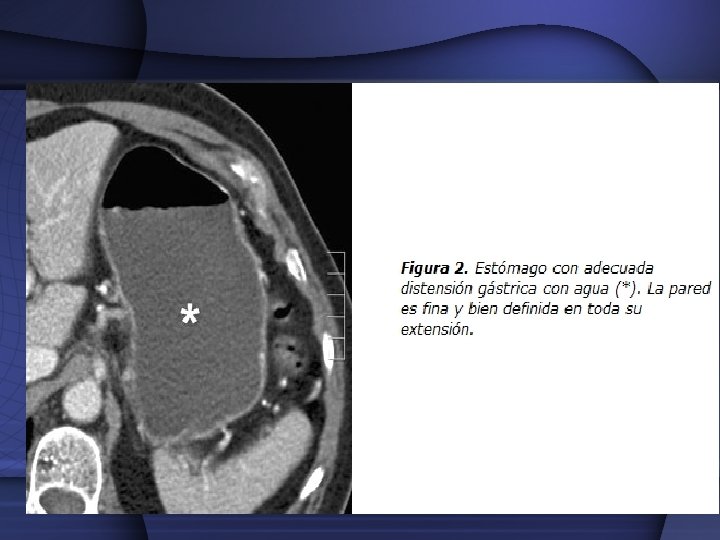

Tomografía abdominal • Hígado con presencia de nódulo de 10 mm en el segmento 3. • Estómago distendido con abundante contenido liquido en el fondo con paredes gruesas a nivel del antro de 12 mm que condicionan estrechez de la luz, infiltran duodeno. • Infiltración de la grasa perigástrica que infiltra páncreas. No se definen adenopatías adyacentes. • CC: quiste hepático. NM gástrico con infiltración a páncreas y grasa perigástrica, cabeza de páncreas prominente.

TAC: signos tomográficos